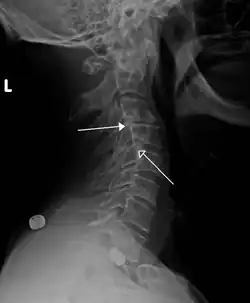

| Grade 1 retrolistheses of C3 on C4 and C4 on C5 | |

A retrolisthesis is a posterior displacement of one vertebral body with respect to the subjacent vertebra to a degree less than a luxation (dislocation). Retrolistheses are most easily diagnosed on lateral x-ray views of the spine. Views where care has been taken to expose for a true lateral view without any rotation offer the best diagnostic quality.

Retrolistheses are found most prominently in the cervical spine and lumbar region but can also be seen in the thoracic area.